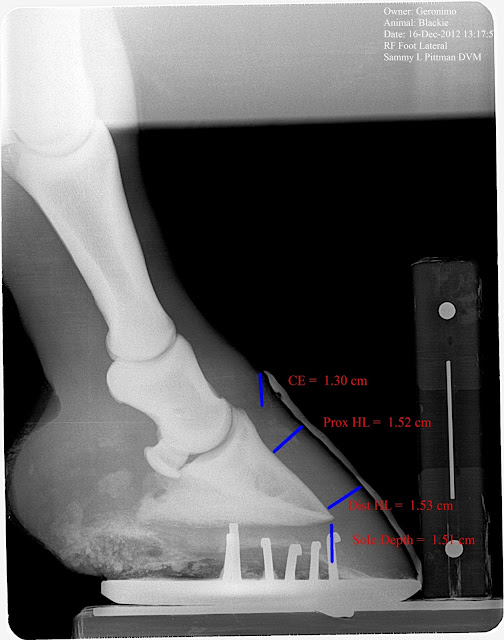

Below are 60 day post radiographs. Note the increased C/E distance, diverging H/L zones (rotation),and loss of sole depth, especially on the Left. No growth is noted on examination of the dorsal hoof wall and about 1/4 in at the heels is noted. Just to recap, we have no measurable displacement of the bone until 60 days into the syndrome but significant vascular changes on day five that continues to fail despite mechanical therapy. If you are waiting to diagnose laminitis based on rotation you are 60 days late in this case.

| 60 day post insult radiograph. Note changes in ce, hl zones and sole depth. |

| 60 Days post initial insult. Note diverging hl zones (some may call rotation) increased in ce and comparable decrease in sole depth. |